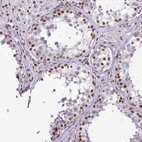

Immunohistochemical staining of human cerebral cortex shows strong nuclear positivity in neuronal and glial cells.